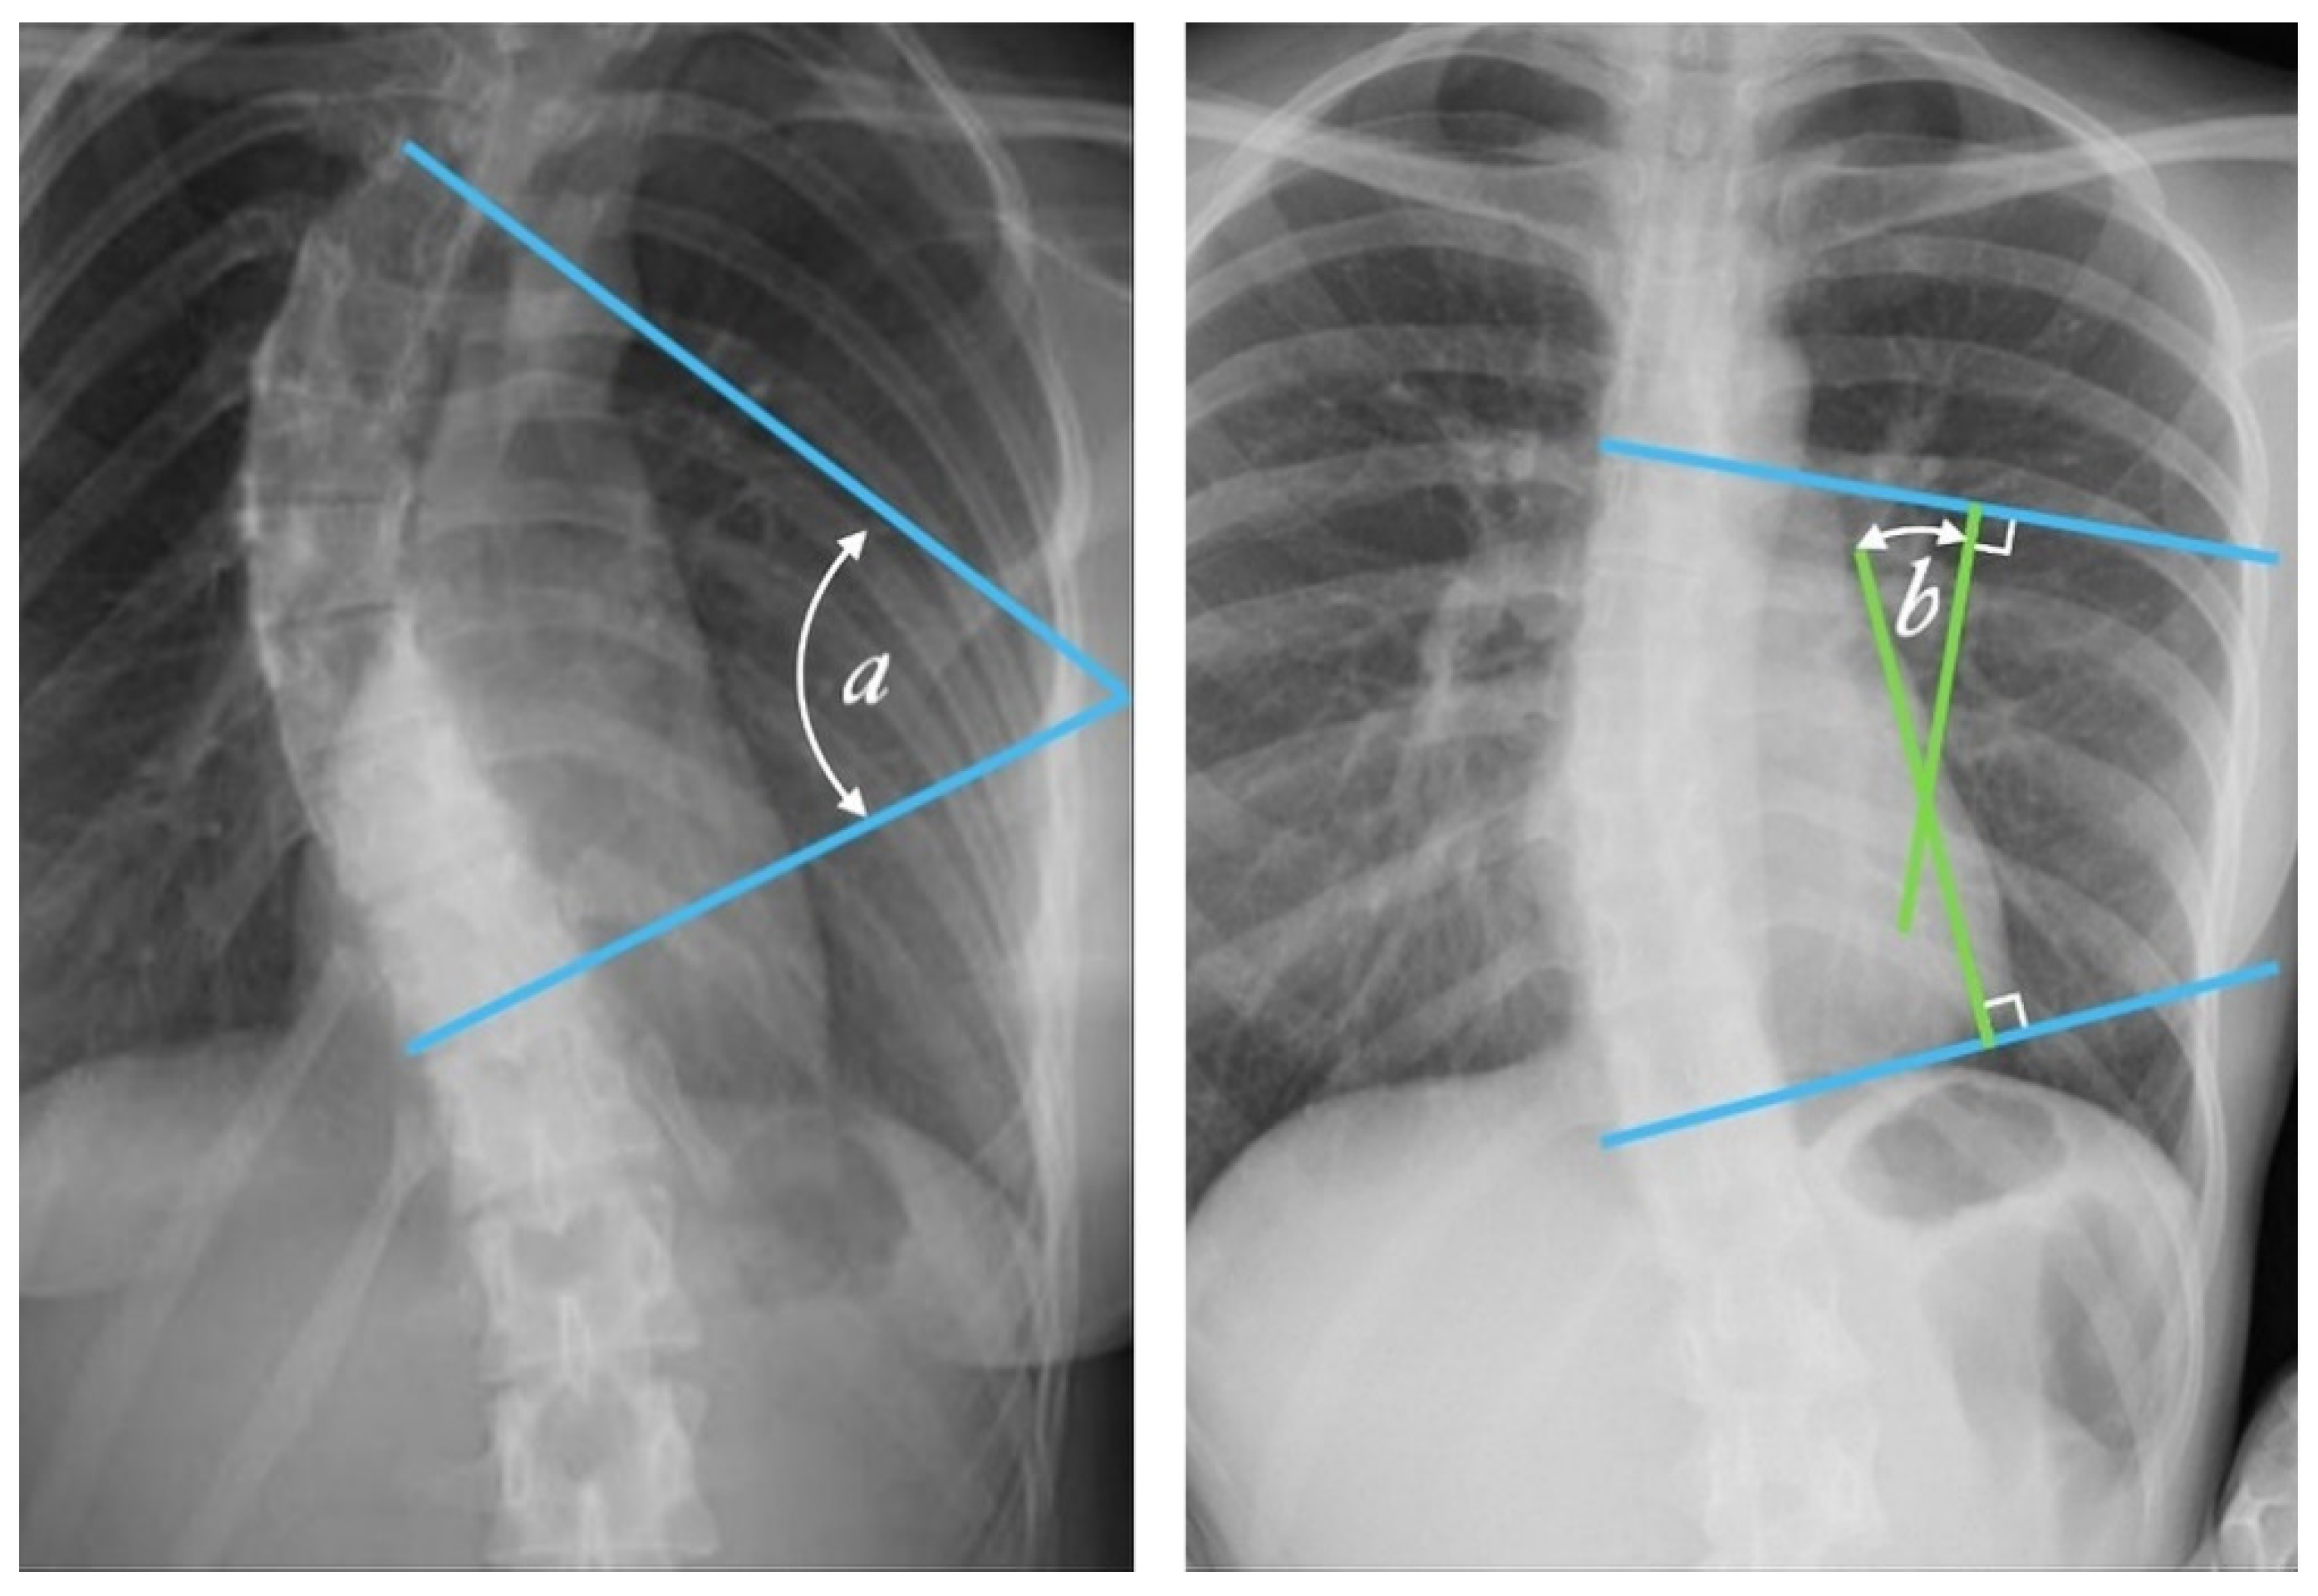

Figure 2.

Cobb angle measurement. Tangential lines are drawn from the superior endplate of the superior vertebra and the inferior endplate of the inferior vertebra. The angle formed at the intersection of these two lines is the Cobb angle. A Cobb angle of at least 10 degrees is necessary for diagnosing scoliosis. (Case courtesy of Assoc Prof Frank Gaillard, Radiopaedia.org, rID: 49374, (CC BY 3.0).) [14] The Cobb angle is defined either as the angle between the tangential lines (angle a) or the angle between two lines drawn perpendicular (solid lines) to the tangents (angle b).

Radiologists always measure the Cobb angle using a protractor after manually selecting the marginal vertebrae, which is presented in Figure 2. This angle is determined by drawing a line tangential at the superior endplate of the upper extremity curvature vertebra and at the inferior endplate of the lower extremity vertebra and then, lines perpendicular to each of the two lines at the most titled vertebrae [12,15]. The Cobb angle is useful in evaluating the initial curve, in determining the increasing magnitude of curves, and in deciding when surgical intervention may be most beneficial to the patient. The accuracy of the Cobb angle measurement mainly depends on the subjective experience of radiologists [13]. This method was used by many clinicians, and they presented the results based on the measurement error. According to some researchers, this error can be up to 11.8° [16]. Previously, measurements were made using a device called a Cobbometer, but the error was so large that it affected the diagnosis and treatment of patients with scoliosis. Thus, other methods of measuring the Cobb angle are developed to better assess the full three-dimensional spinal deformity with the modern imaging diagnostic techniques that allow 3D reconstructions [17]. Both the Cobb and Ferguson methods are based on manual identification of the end vertebrae. However, due to better reproducibility, easier application, and the ability to measure larger angles for more severe spinal curvatures, the Cobb method was preferred. The Cobb method has been standardized, and the key aspect of “reproducibility” has been tested and confirmed in numerous studies [18,19,20,21,22,23,24,25,26].